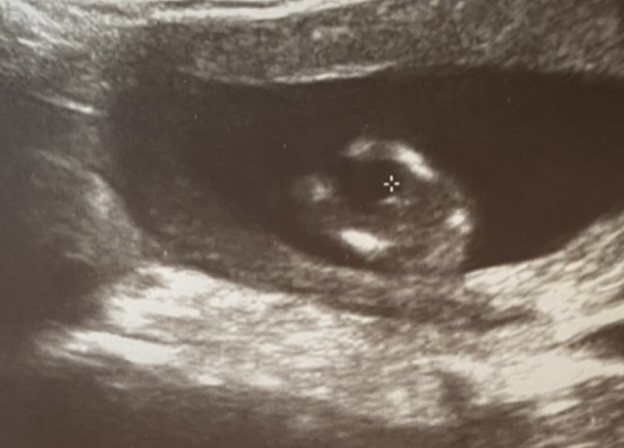

Cinsiyet sizce?

Merhaba 12+4 uz.Doktor %60 erkek dedi ama size de sormak istedim.Sizce?🙈😍